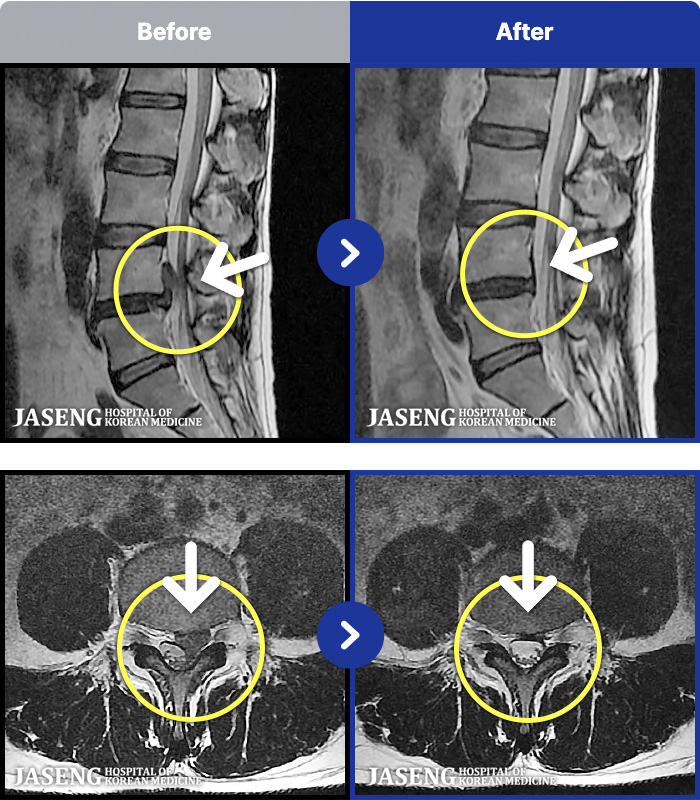

1,304 MRI ũ ʸ Ȯϼ.

[뱸] 19.11.28~25.05.06